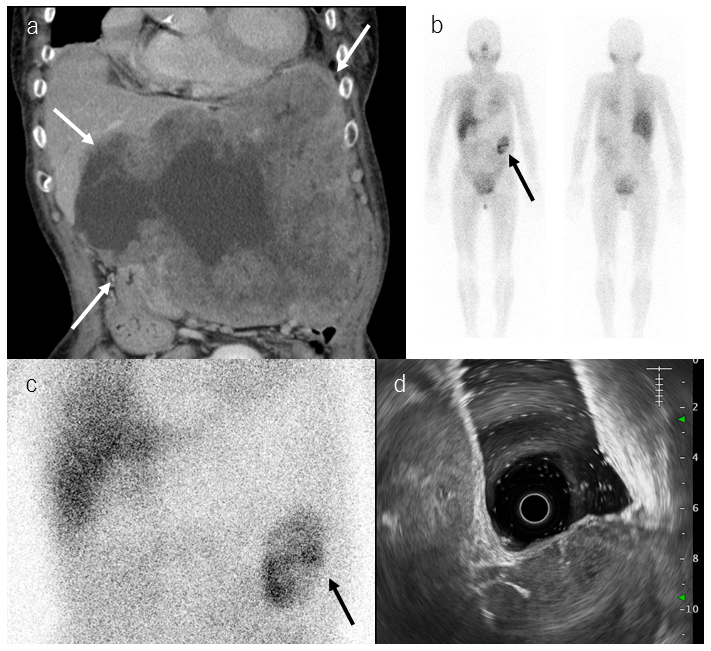

Meta-iodobenzylguanidine (MIBG) is an analog of norepinephrine and guanethidine, and MIBG scintigraphy is useful to diagnose tumors of the sympathetic nervous system, such as pheochromocytoma, paraganglioma, and neuroblastoma. To date, there have been few reports of MIBG accumulation in gastrointestinal stromal tumors (GISTs), so the mechanism and frequency of MIBG accumulation in GISTs are unknown. Herein, we report and discuss three cases of GIST in which scintigraphy that was performed to exclude pheochromocytoma showed MIBG accumulation.